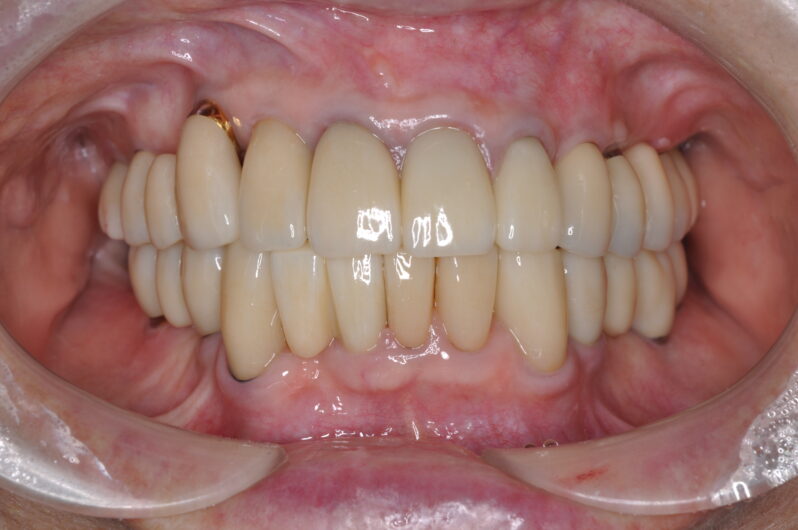

*術後10年の写真

10年前、この患者様は大きな決断をされました。そして今、その決断が正しかったことを、笑顔とともに実証してくださっています。

これがインプラント治療の大きなメリットの一つです。天然歯が失われても、既存のインプラントを土台として、新しいブリッジを作製することができるのです。大掛かりな手術を追加することなく、機能的で審美的な治療が可能になりました。